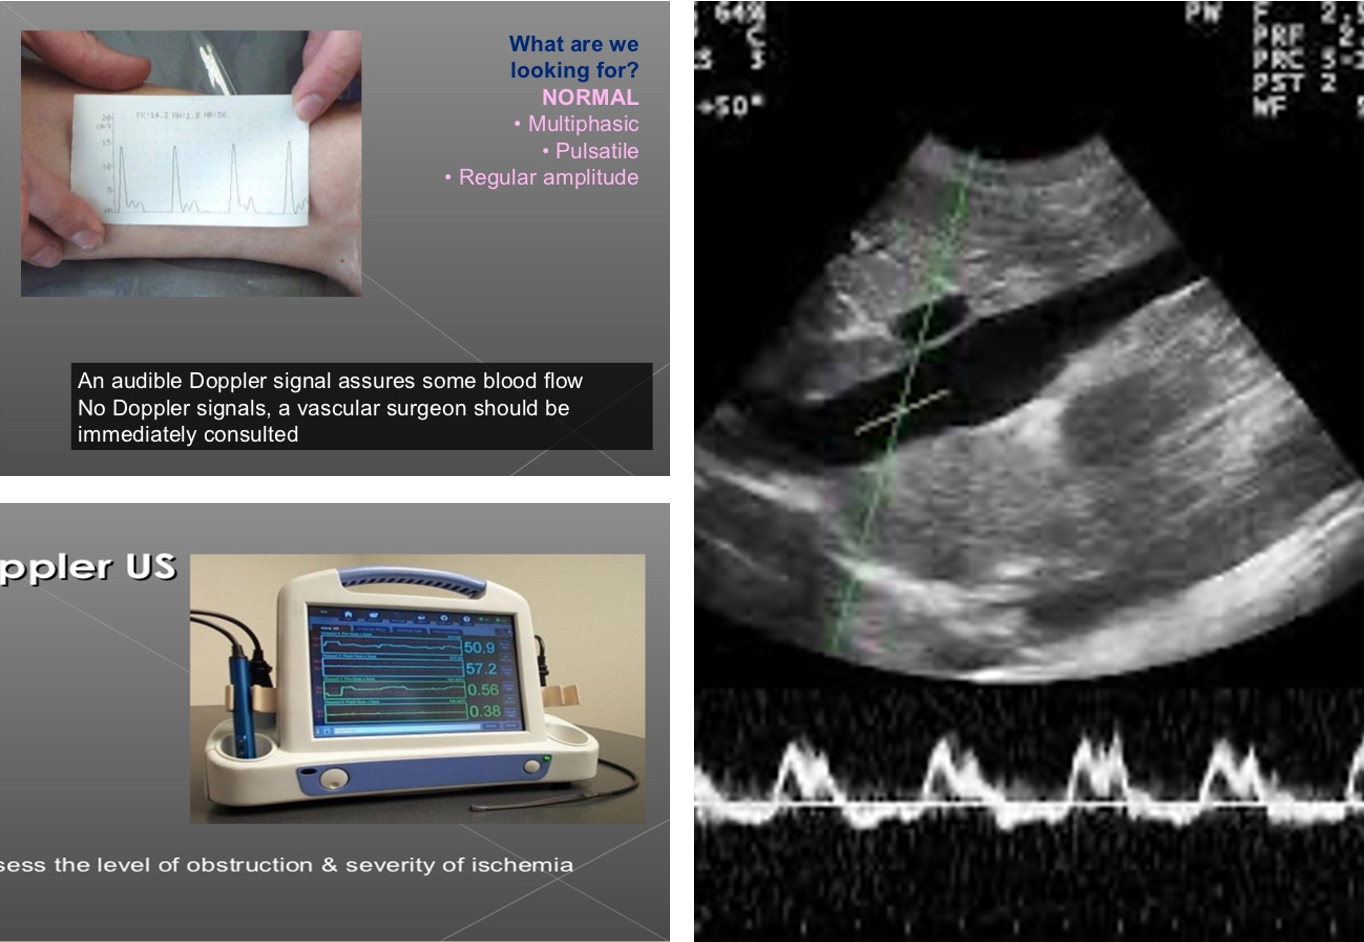

Doppler Vs Dopplux

Multiphasic normal one -

duplex waves + picture